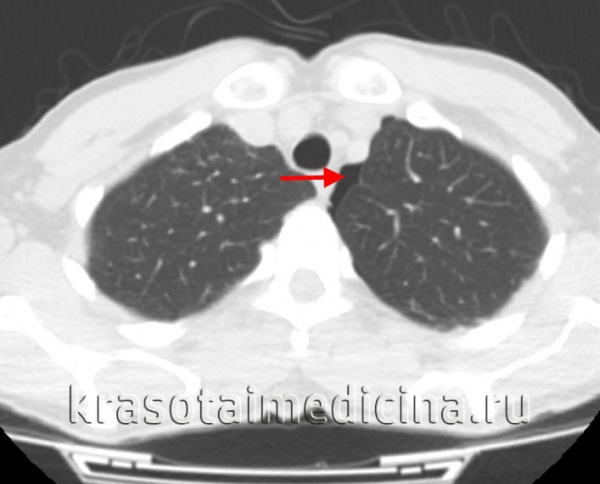

По данным томографии в правой плевральной полости имеется большое количество жидкости — до уровня второго ребра.